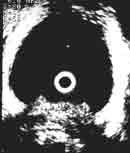

На Рис. 4 представлены эхограммы одного больного — трансабдоминальное и эндовезикальное исследование. Трансабдоминальное сканирование в данном случае не позволяет судить о глубине инвазии, а при эндовезикальном исследовании выявлена начинающаяся инвазия мышечного слоя, причем место инвазии визуализируется как гипоэхогенный участок на фоне гиперэхогенной мышечной ткани (стадия Т2а). Более четко визуализируется инвазия глубокого мышечного слоя (стадия Т2в) (Рис. 5).

Увеличить

Рис. 4. Рак мочевого пузыря стадия Т2а (стрелкой указана начинающаяся инвазия мышечного слоя).

(Слева) Трансабдоминальное сканирование.

(Справа) Эндовезикальное сканирование.